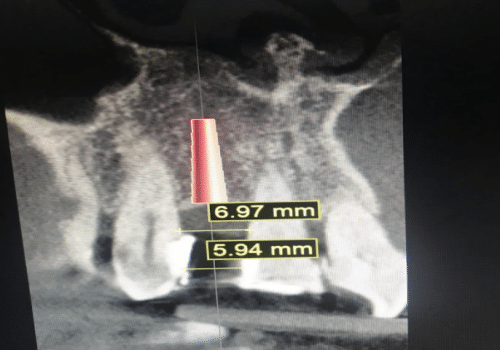

Los implantes dentales ofrecen una solución permanente para reemplazar los dientes perdidos, utilizando dispositivos de titanio que simulan la raíz dental.

Los implantes dentales ofrecen una solución permanente para reemplazar los dientes perdidos, utilizando dispositivos de titanio que simulan la raíz dental.

En AIEN, contamos con un equipo especializado en implantología para ofrecerte tratamientos personalizados que devuelven la plenitud a tu sonrisa y mejoran tu calidad de vida.